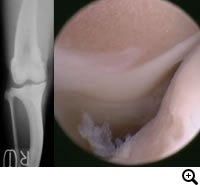

OCD(離断性骨軟骨症)とは

大腿骨骨頭の関節軟骨が成長障害により厚みを増し、損傷を受けやすくなり、軟骨が浮きあがりはがれることで痛みを生じます。

診断

レントゲン検査、関節鏡検査

治療

OATS(自家骨軟骨移植)など。軟骨の欠損部に別の部位から採取した本人の正常な軟骨を移植し、関節面での接触を良くし、痛みを取り除きます。大型犬の成長期の跛行は消炎鎮痛剤等による対症療法ですませず、跛行原因の早期診断、早期治療が重要です。